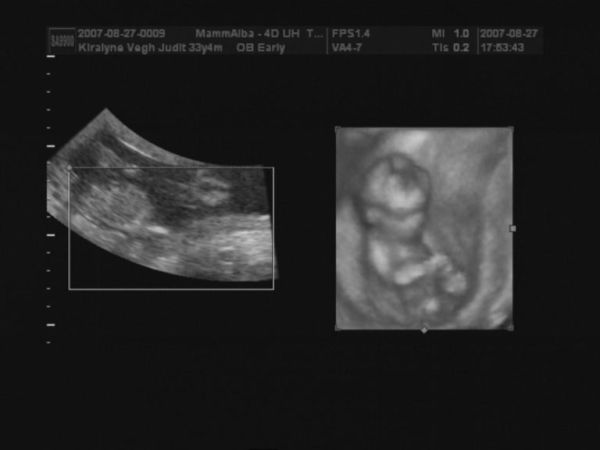

Megjöttünk 4D-ről.

CRL 9,54

BPD 2,83

A gép 14+6 napra dobta ki a korát, ami jó is.

Pulzus 167 percenként

Jelenleg kuki nem látható. Szóval remény még mindig van.

alsónézet, itt kellene lennie a kukinak.

A feneke és a lábacskái látszanak.

Kép

2D oldalról